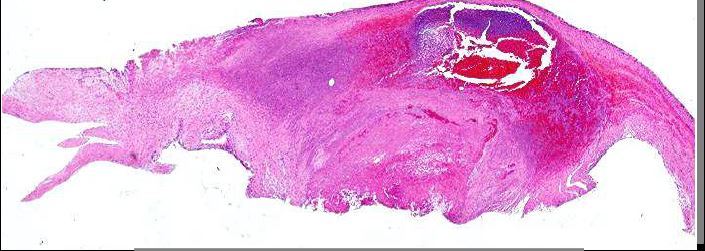

Q

What cardiac tumor is being shown?

A

Rhabdomyoma

MOST COMMONLY IN LEFT VENTRICLE

Most common primary cardiac tumor of

infancy and childhood

May be sporadic, but >50% associated with TS

Eosinophilic, polygonal cells with large glycogen-rich cytoplasmic vacuoles with stranding “spider cells”